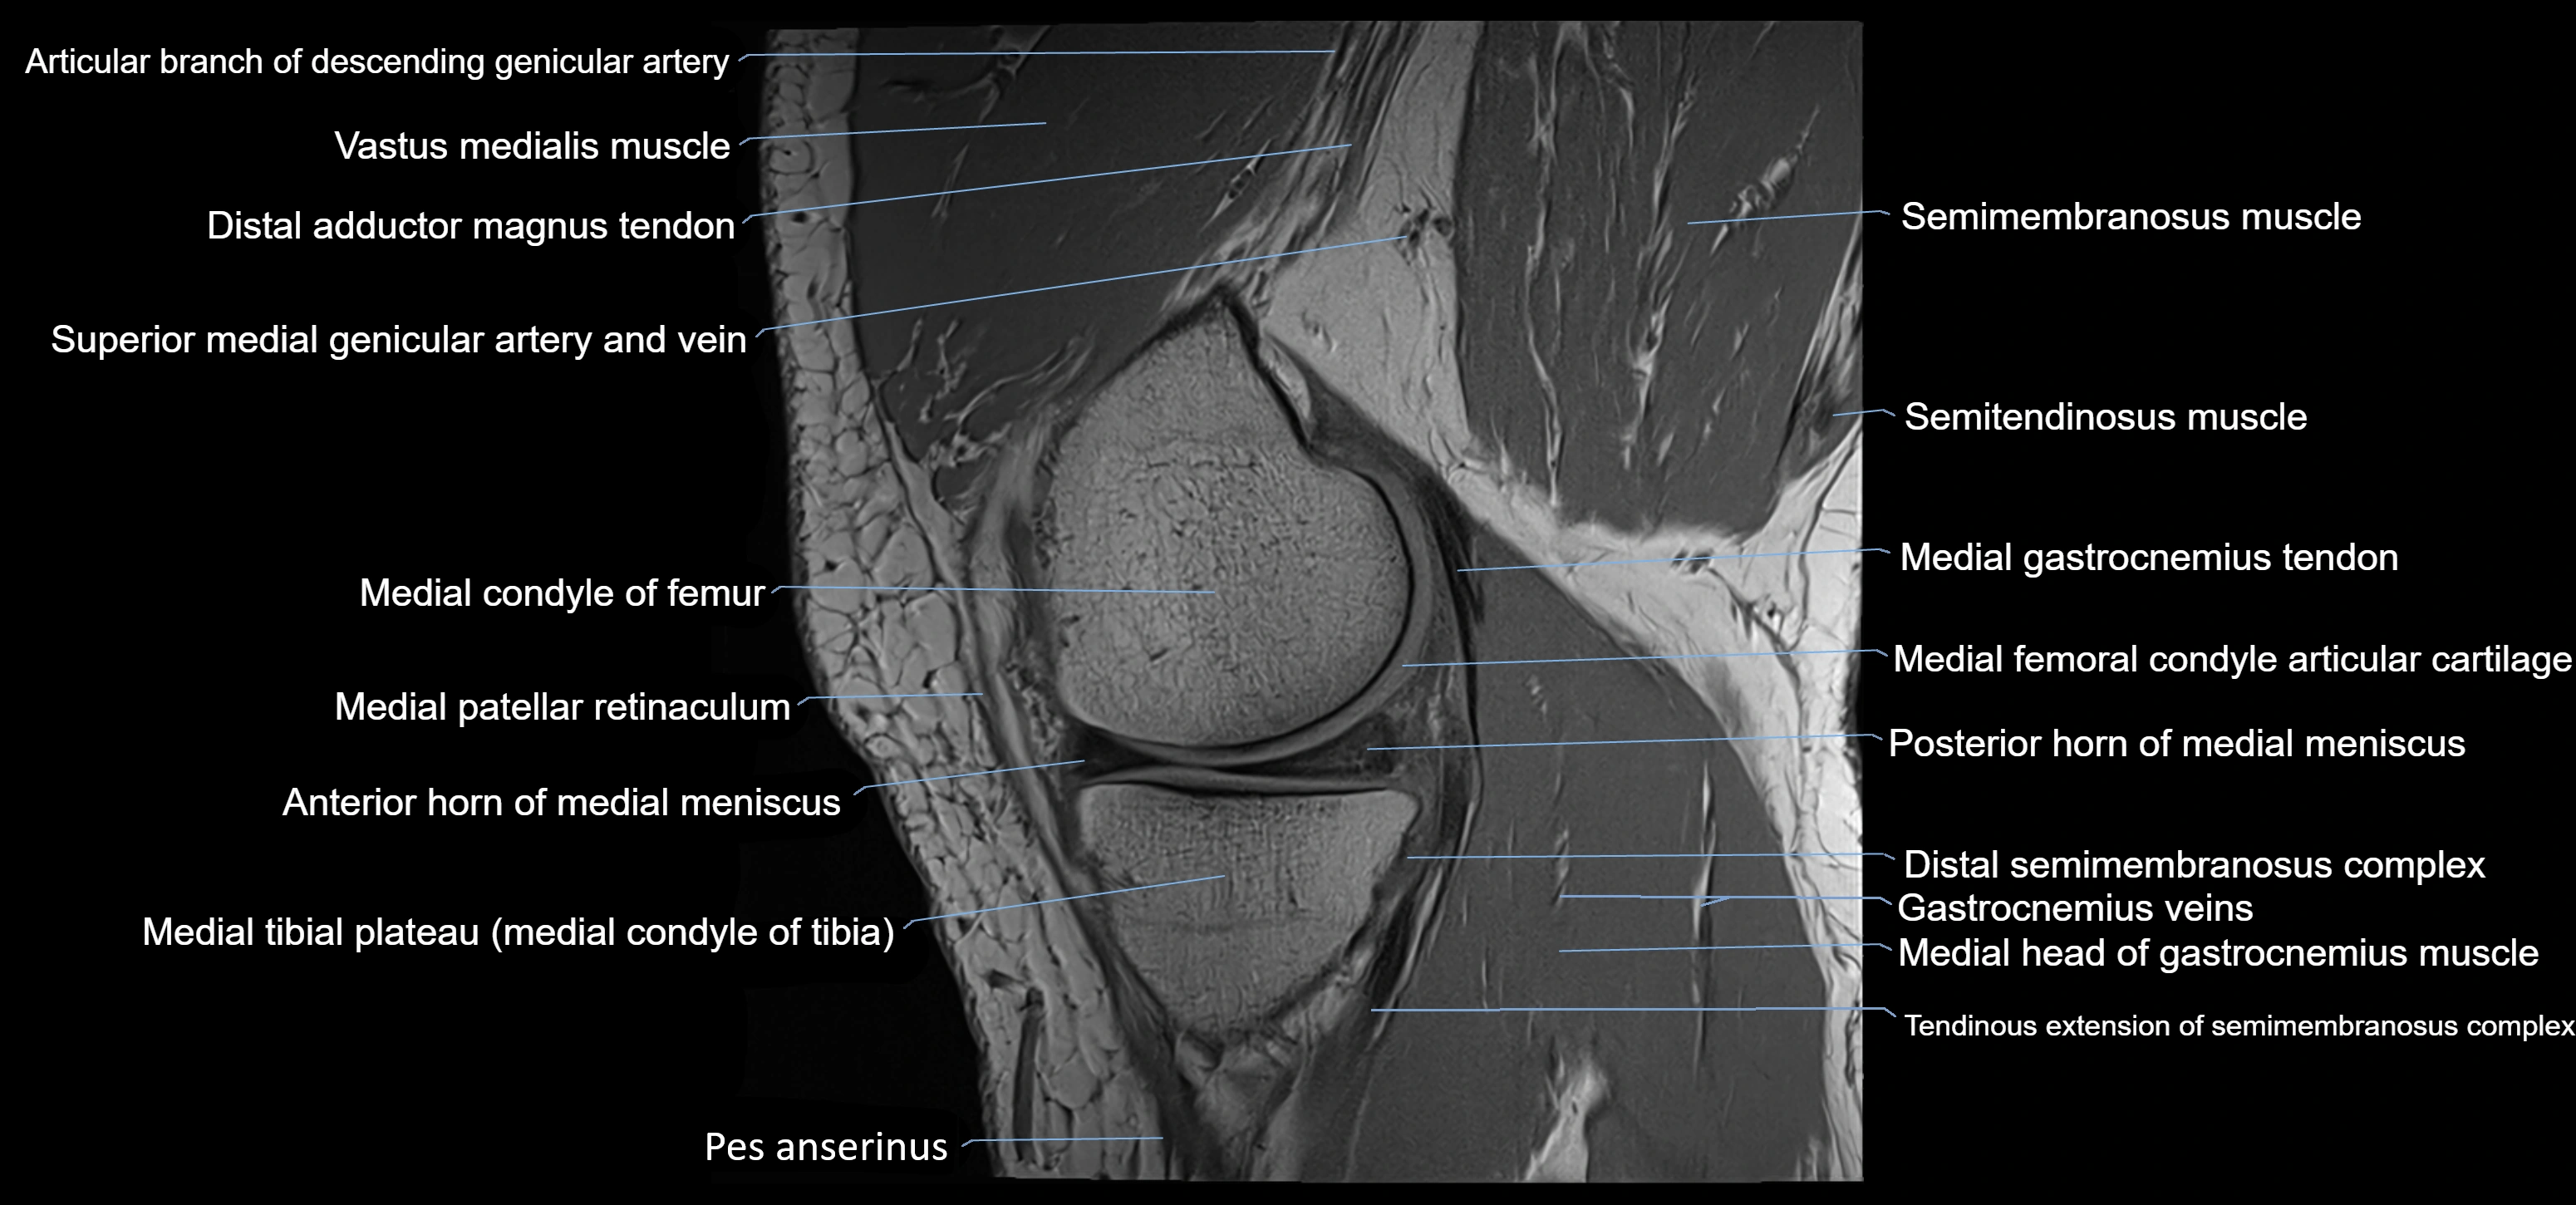

- Vastus medialis muscle

- Distal adductor magnus tendon

- Superior medial genicular artery

- Superior medial genicular vein

- Medial condyle of femur

- Medial patellar retinaculum

- Anterior horn of medial meniscus

- Posterior horn of medial meniscus

- Distal semimembranosus tendon

- Medial gastrocnemius tendon

- Medial head of gastrocnemius muscle

- Medial condyle of tibia